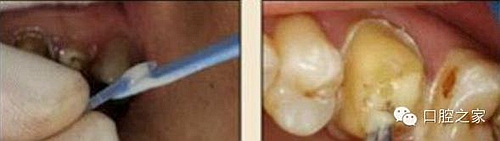

10.毛刷的選用

圖20:毛刷應(yīng)用(錯(cuò)誤) 圖21:根管專用毛刷

市場(chǎng)上毛刷的種類繁多,臨床應(yīng)用比較雜亂。冠部牙體組織或各種修復(fù)體涂抹粘接劑時(shí),由于粘接面視野清晰、范圍大,對(duì)毛刷的選擇一般無(wú)嚴(yán)格要求,臨床大多使用圓球形或鬃束狀毛刷;纖維樁修復(fù)時(shí),由于根管樁道有深度且視野差,以上兩種毛刷很難伸入狹窄的樁道深部,無(wú)法保證粘接劑在整個(gè)樁道內(nèi)壁被均勻地涂抹(圖 20)。纖維樁粘接時(shí)應(yīng)使用根管專用微型毛刷(圖 21),其形態(tài)和長(zhǎng)度與樁道吻合,毛刷頭部可彎曲控制,可到達(dá)較深的根管底端,有利于粘接劑的均勻涂布。某些根管毛刷采用納米級(jí)刷毛,根管涂擦?xí)r可進(jìn)入牙本質(zhì)小管和側(cè)枝根管,能較好地提高粘接效果。 ##pages##